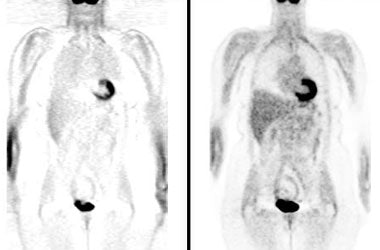

| BGO versus LSO detector: The images below were acquired in 2D mode with a scan time of 5 min/bed emission and 3 min/bed transmission. The upper row of images were acquired on a BGO camera system and the lower row of images were acquired on a ECAT Accel LSO PET camera system. The data was reconstructed using normalized attenuation weighted OS-EM reconstruction. Image courtesy of Northern California PET Imaging Center, Sactamento, CA and CTI, The Power Behind PET. |